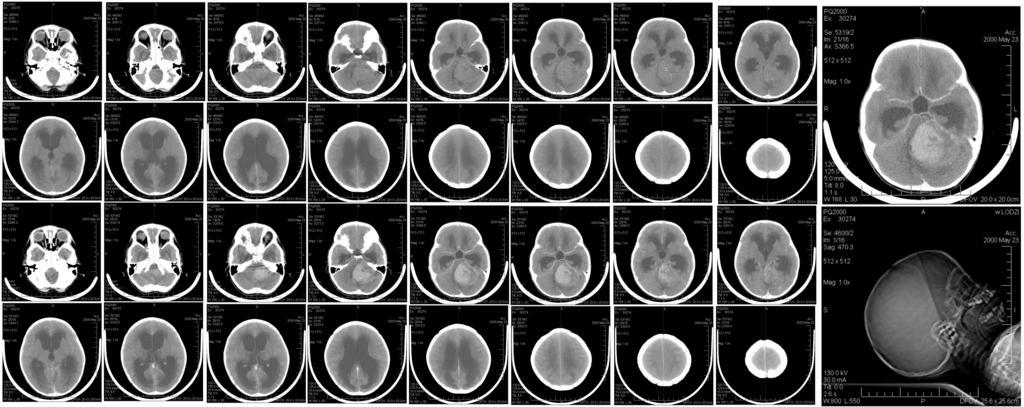

MAKE A MEME View Large Image CT brain scan of child with medulloblastoma and resulting hydrocephalus.jpg Six-year-old girl with medulloblastoma Medulloblastoma Neuroradiology

Keywords: CT brain scan of child with medulloblastoma and resulting hydrocephalus.jpg Six-year-old girl with medulloblastoma Medulloblastoma Neuroradiology